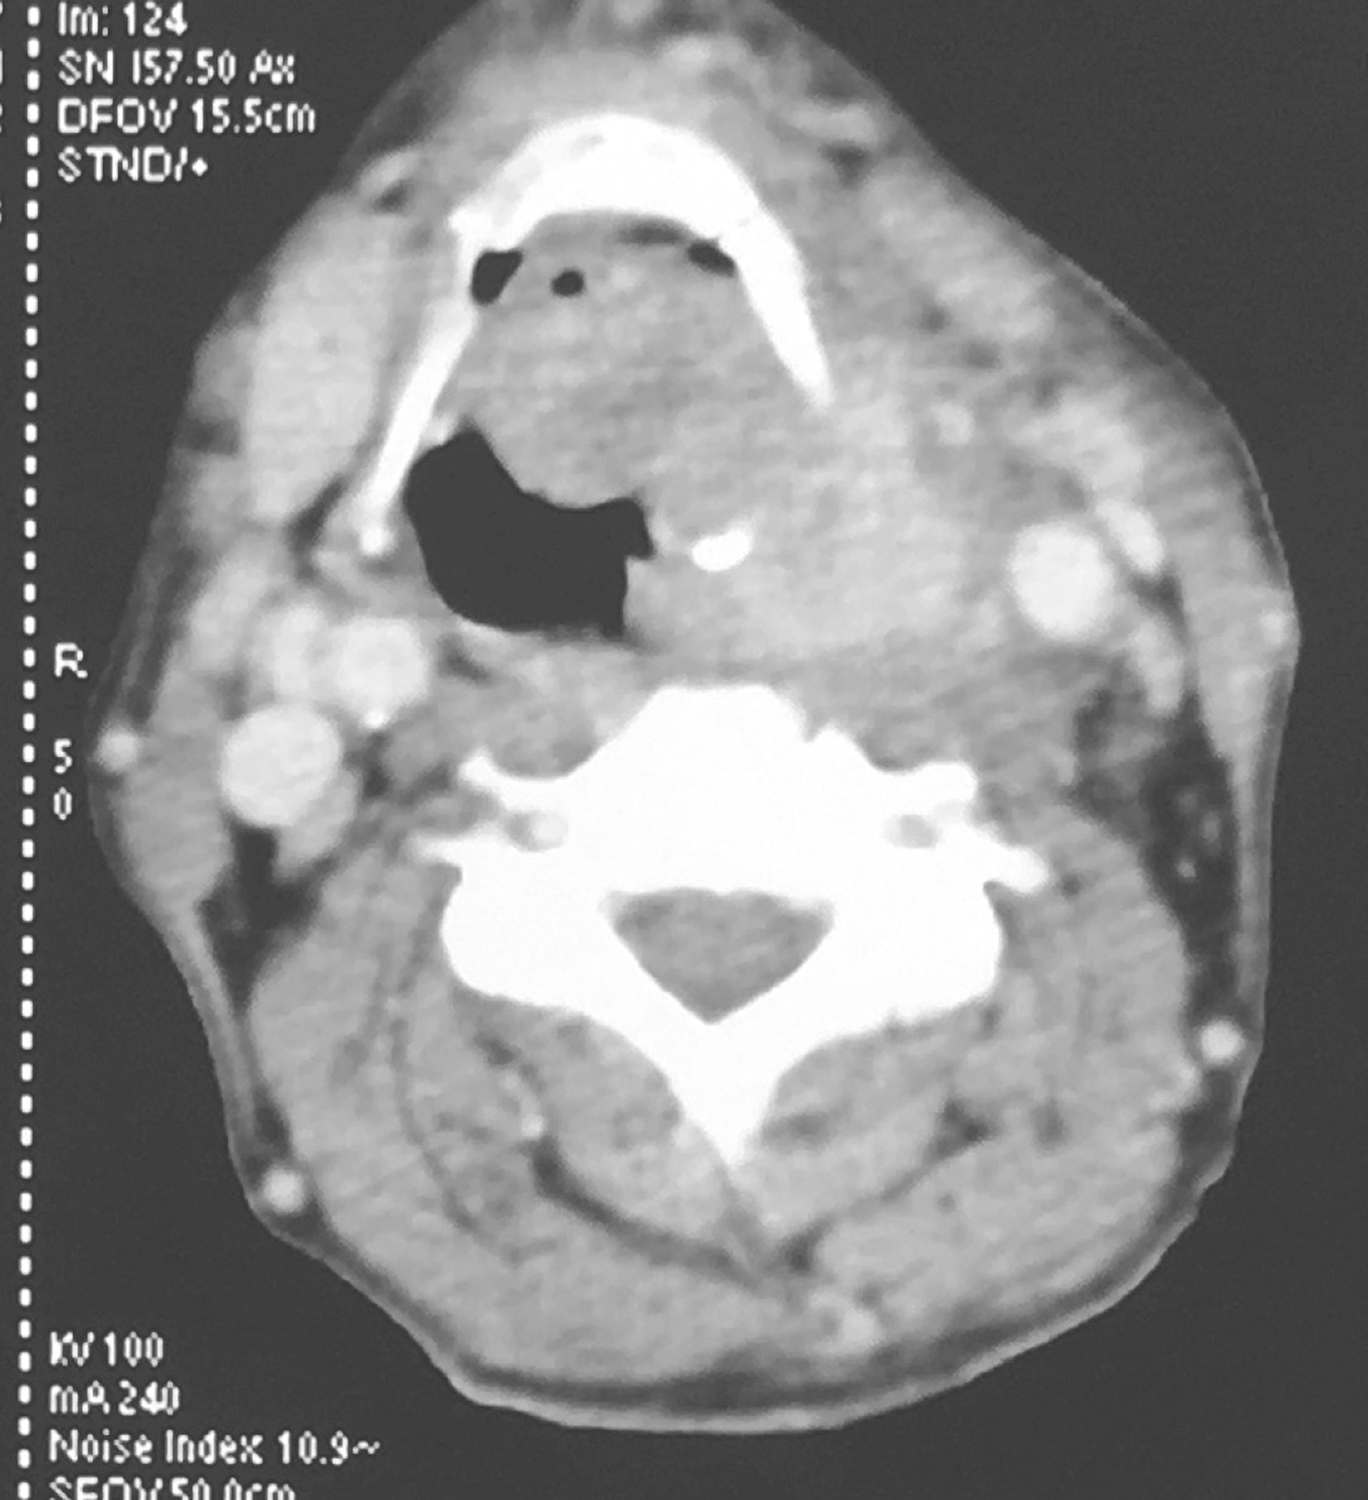

①下咽部左梨状窝区可见软组织密度影,增强扫描可强化,向内累及左侧半喉,侵犯会厌前间隙、声门旁间隙,肿瘤侵透甲状软骨板、舌骨、累及咽侧壁及下咽后壁(图1、图2),向下累及环后区及颈段食管,向外侵犯喉外肌肉及颈前软组织。颈动脉鞘周围多枚肿大淋巴结,部分融合,边界不清,与咽喉肿瘤及颈前肌肉融合,右侧甲状腺受侵(图3),颈内静脉闭塞(图4),颈总动脉与肿瘤边界不清。右侧颈鞘周围也可见多枚肿大淋巴结,增强扫描可见强化。②双肺纹理增粗,双肺野及纵隔内未见异常。

影像学诊断:符合下咽部恶性肿瘤累及喉,双颈部多发淋巴结转移表现。

图1下咽部左梨状窝区可见软组织密度影,增强扫描可强化

图2向内累及左侧半喉,侵犯会厌前间隙、声门旁间隙,肿瘤侵透甲状软骨板、舌骨、累及咽侧壁及下咽后壁